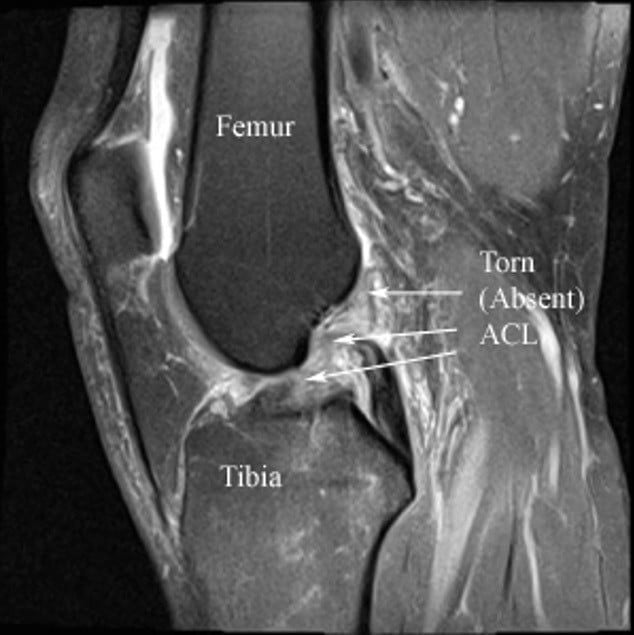

Hình 3: Hình ảnh MRI đứt dây chằng chéo trước

Khi có các triệu chứng trên các bác sĩ sẽ cho chỉ định chụp X-quang và MRI khớp gối. Chụp X-quang giúp chẩn đoán các trường hợp bong dứt điểm bám và tình trạng xương.

Chụp cộng hưởng từ khớp gối ngoài giúp chẩn đoán đứt dây chằng còn giúp phát hiện các tổn thương kèm theo như sụn chêm, sụn khớp, dây chằng chéo sau, dây chằng bên…